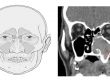

80% опухолей слюнных желез возникают из передней (околоушной) слюнной железы и в большинстве случаев представляют собой односторонние медленнорастущие образования. Примерно 10% происходит из подчелюстно-лицевой слюнной железы, а остальная часть – из подъязычных и малых слюнных желез. 80% всех опухолей слюнных желез являются доброкачественными, а 20% – злокачественными. Наиболее распространенная доброкачественная опухоль называется плеоморфной аденомой, а вторая по распространенности опухолью – опухолью Вартина. Наиболее распространенными злокачественными опухолями являются мукоэпидермоидный рак, аденоидно-кистозный рак и аденокарцинома.

Местоположение образования в головном мозге пациента, когда оно было замечено, скорость роста и дополнительные жалобы (например, образование боли, паралич лицевого нерва) должны быть поставлены под сомнение в анамнезе. При обследовании оценивается расположение новообразования, его размер, твердость, размер, функции лицевого нерва и состояние кожи над опухолью. Для окончательного диагноза проводится вмешательство, называемое тонкоигольной аспирационной биопсией под ультразвуковым контролем, и взятые образцы отправляются на гистопатологическое исследование. Хотя патологический результат, полученный с помощью этой процедуры, не является определенным результатом, он все же дает важную информацию для руководства врачом, который будет продолжать лечение.